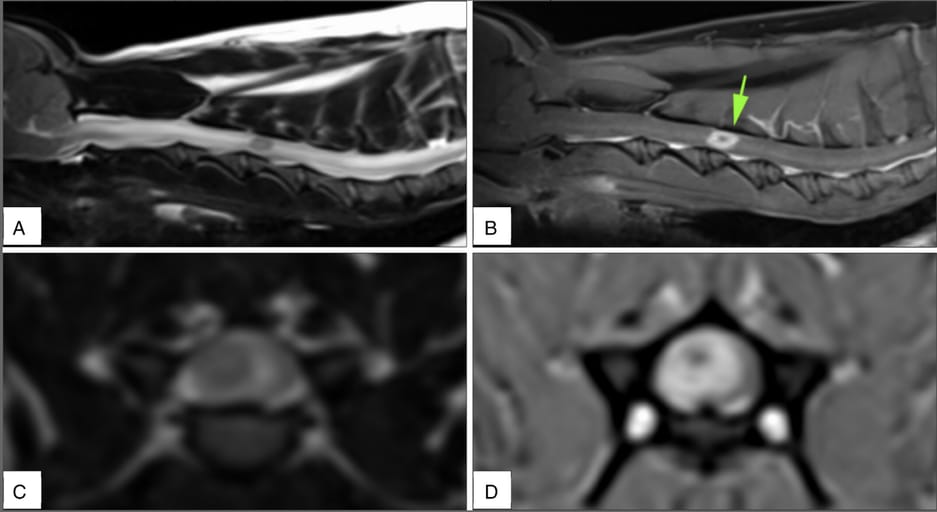

In Case 1, MRI revealed an intramedullary lesion in the cervical spinal cord with marked ring enhancement and surrounding edema. Despite empirical antibiotic and corticosteroid therapy, the dog's condition deteriorated, leading to euthanasia. Histopathology identified a pyogranulomatous myelitis with fungal elements, and PCR confirmed C. bantiana. In Case 2, the cat displayed thoracolumbar myelopathy with systemic signs. Post-mortem revealed vertebral osteomyelitis compressing the spinal cord and disseminated fungal lesions in multiple organs. Fungal hyphae were observed in urine and tissues, and PCR of the cultured organism confirmed C. bantiana.

Sagittal T2-weighted image (A), sagittal T1-weighted post-contrast image (B), transverse T2-weighted image (C) and transverse T1-weighted post-contrast image (D). The lesion can be seen as a focal rounded intramedullary abnormality with marked perilesional T2-weighted hyperintensity and ring contrast enhancement (arrow). All images were obtained with 1.5 T MRI.